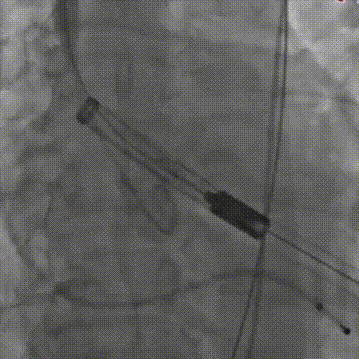

手术关键步骤

A.预扩张,并同时行主动脉造影

B. 冠脉保护:导丝、球囊、Guidezilla、位于LAD;Guiding回撤至升主动脉适当位置

C. 应用交界贴合技术调整人工瓣膜,标准位释放瓣膜并行释放后造影